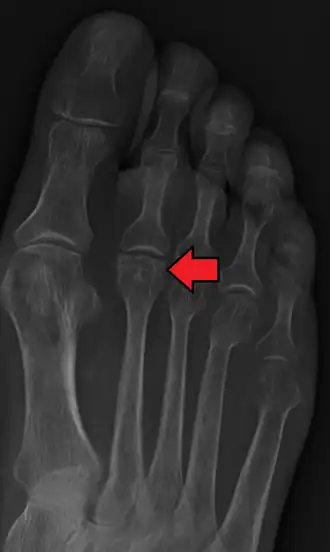

Radiographie d'une maladie de Freiberg.

Le diagnostic est clinique et peut être confirmé par des images radiographiques, par la scintigraphie osseuse ou par l'imagerie par résonance magnétique[2]. Il existe cinq stades de maladie radiologique, appelés stades de Smillie, et pouvant aider à la planification chirurgicale[4].